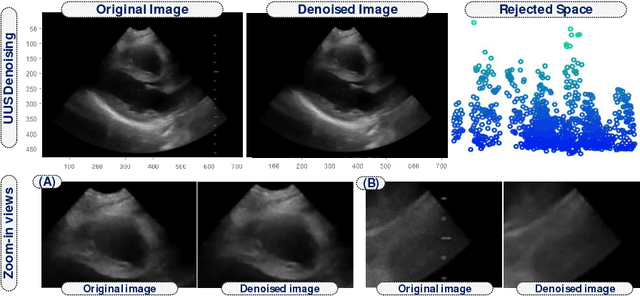

Abstract:Cardiac motion estimation is an important diagnostic tool to detect heart diseases and it has been explored with modalities such as MRI and conventional ultrasound (US) sequences. US cardiac motion estimation still presents challenges because of the complex motion patterns and the presence of noise. In this work, we propose a novel approach to estimate the cardiac motion using ultrafast ultrasound data. -- Our solution is based on a variational formulation characterized by the L2-regularized class. The displacement is represented by a lattice of b-splines and we ensure robustness by applying a maximum likelihood type estimator. While this is an important part of our solution, the main highlight of this paper is to combine a low-rank data representation with topology preservation. Low-rank data representation (achieved by finding the k-dominant singular values of a Casorati Matrix arranged from the data sequence) speeds up the global solution and achieves noise reduction. On the other hand, topology preservation (achieved by monitoring the Jacobian determinant) allows to radically rule out distortions while carefully controlling the size of allowed expansions and contractions. Our variational approach is carried out on a realistic dataset as well as on a simulated one. We demonstrate how our proposed variational solution deals with complex deformations through careful numerical experiments. While maintaining the accuracy of the solution, the low-rank preprocessing is shown to speed up the convergence of the variational problem. Beyond cardiac motion estimation, our approach is promising for the analysis of other organs that experience motion.